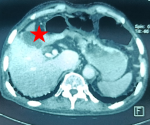

After five days, the patient was better, afebrile and asymptomatic. He was discharged home receiving oral ciprofloxacin (750 mg twice daily). After three months, on follow-up, he did not present complaints but the abdominal CT scan showed a hypodense hepatic collection surrounded by a wall enhanced after injection of contrast medium at the level of the vesicular bed measuring 53 x 28 mm (Figure 2). Sulfamethoxazole trimethoprim (800mg/160mg) 3 times daily was added to ciprofloxacin. On the 4th month, an ultrasound showed that the abscess was significantly decreased in size. We stopped the antibiotherapy. Three months later, an abdominal CT scan was performed, showed a complete disappearance of the abscess.

Figure 2: course of liver abscess after surgical and 3 months of antibiotic treatment: axial section (red star)